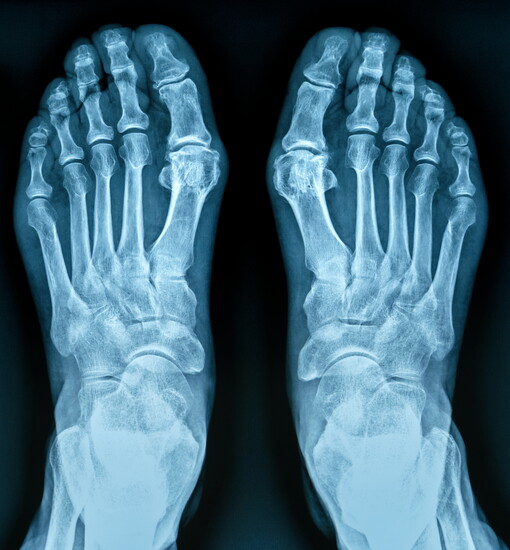

Brittni Warnock, practice manager, receptionist and Dr. Warnock's spouse, says the team provides care for various types of podiatric conditions, including Achilles tendonitis; athlete's foot; bunions; diabetic foot care; flatfoot (fallen arches); ingrown toenails; metatarsalgia; onychomycosis (nail fungus); plantar fasciitis; sprains/strains and toe deformities.

Podiatry is a heavily procedure- and surgical-oriented medical care in the office. Dr. Warnock points to treatments such as injections, trimming calluses, freezing warts and helping patients to regain mobility.